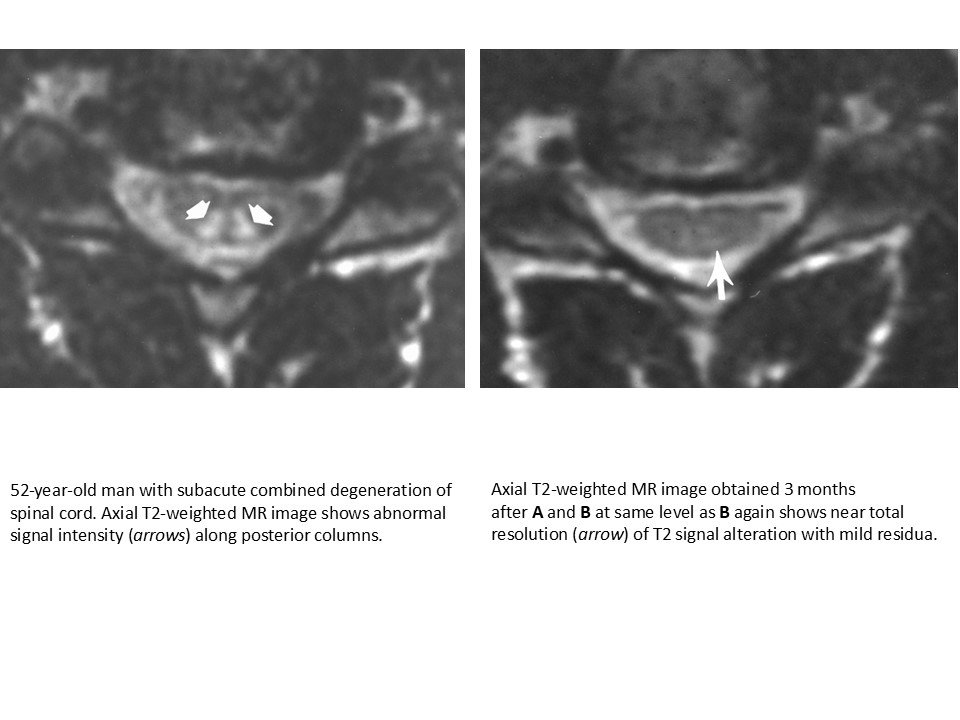

• Symmetric posterior column T2 hyperintensity.

• Inverted V sign on axial images.

• No enhancement.

• No cord compression.

• Seen in vitamin B12 deficiency.

• 52-year-old man with subacute combined degeneration of spinal cord. Sagittal T2-weighted MR image shows abnormally increased signal intensity (arrows) along posterior columns of spinal cord extending from C1 through C6.

• Follow-up sagittal T2-weighted MR image obtained 3 months after A and B shows near total resolution of signal abnormality.